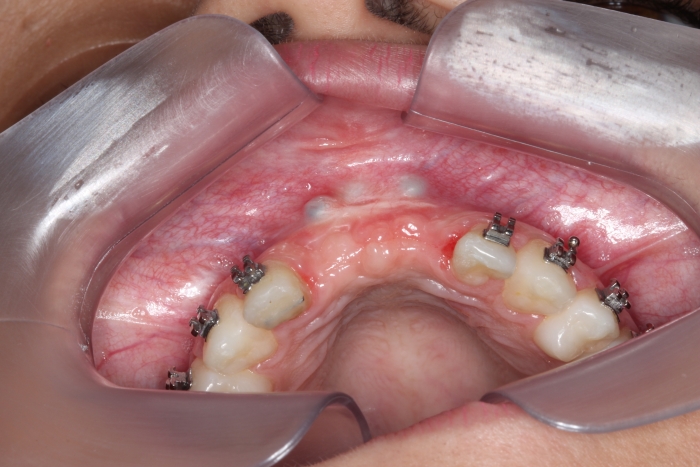

Imagem após enxerto ósseo